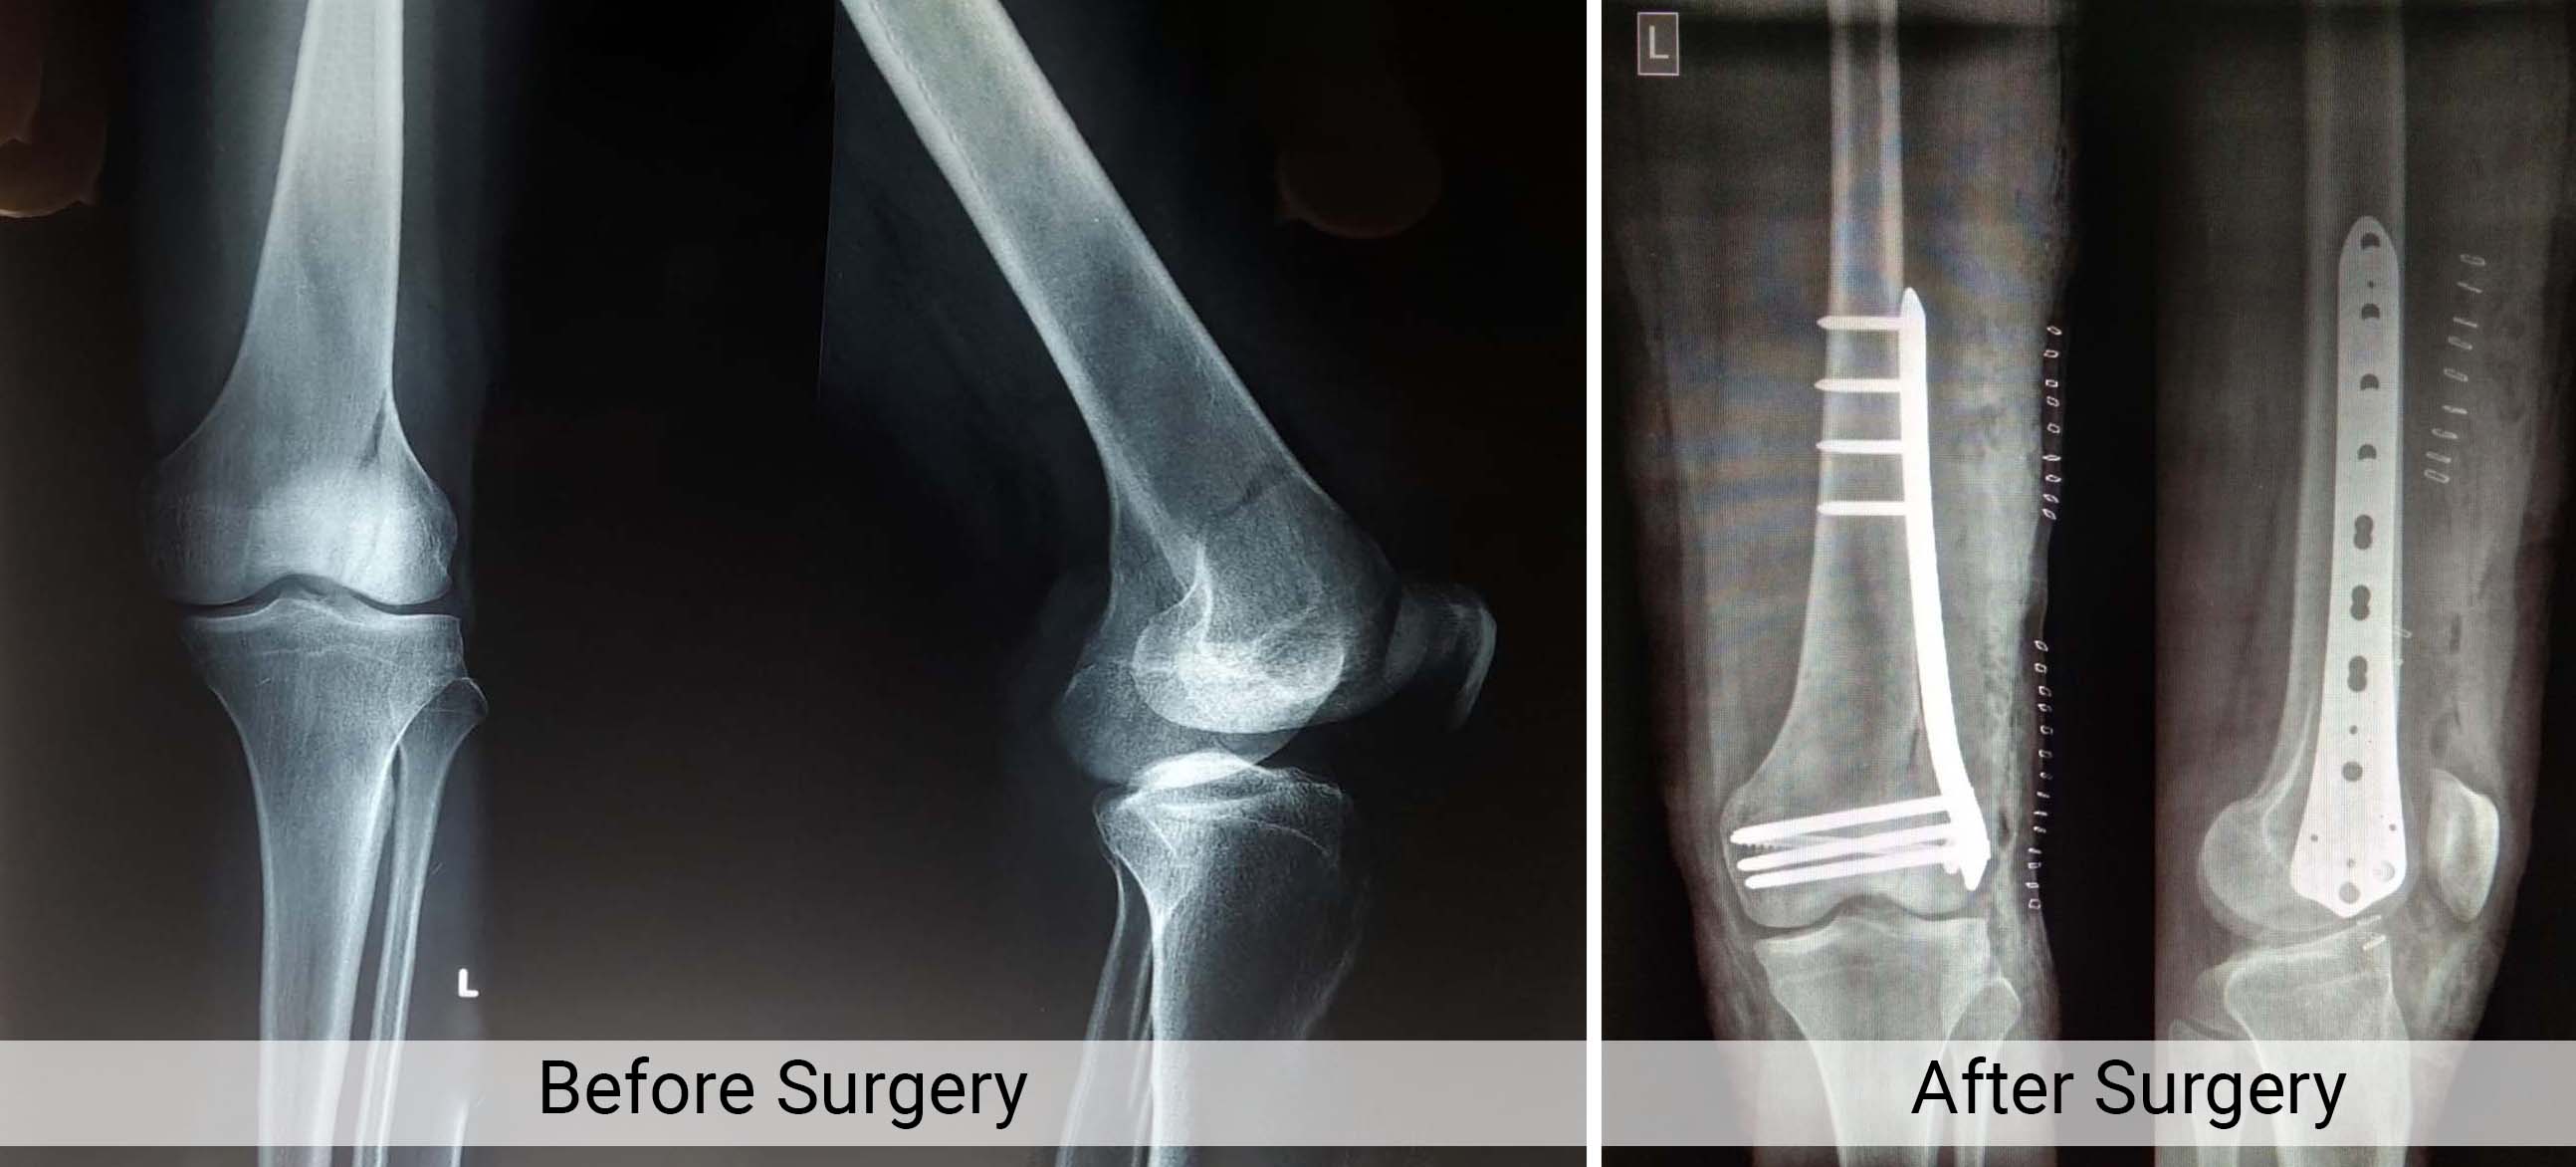

Knee and Hip Replacement

Trauma Fracture